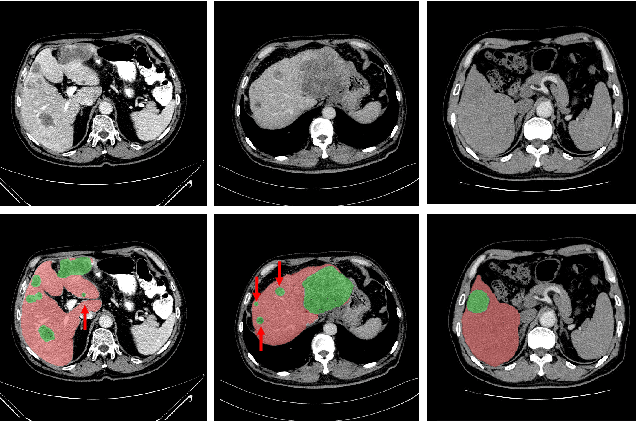

Abstract:Purpose: Automated liver tumor segmentation from Computed Tomography (CT) images is a necessary prerequisite in the interventions of hepatic abnormalities and surgery planning. However, accurate liver tumor segmentation remains challenging due to the large variability of tumor sizes and inhomogeneous texture. Recent advances based on Fully Convolutional Network (FCN) for medical image segmentation drew on the success of learning discriminative pyramid features. In this paper, we propose a Decoupled Pyramid Correlation Network (DPC-Net) that exploits attention mechanisms to fully leverage both low- and high-level features embedded in FCN to segment liver tumor. Methods: We first design a powerful Pyramid Feature Encoder (PFE) to extract multi-level features from input images. Then we decouple the characteristics of features concerning spatial dimension (i.e., height, width, depth) and semantic dimension (i.e., channel). On top of that, we present two types of attention modules, Spatial Correlation (SpaCor) and Semantic Correlation (SemCor) modules, to recursively measure the correlation of multi-level features. The former selectively emphasizes global semantic information in low-level features with the guidance of high-level ones. The latter adaptively enhance spatial details in high-level features with the guidance of low-level ones. Results: We evaluate the DPC-Net on MICCAI 2017 LiTS Liver Tumor Segmentation (LiTS) challenge dataset. Dice Similarity Coefficient (DSC) and Average Symmetric Surface Distance (ASSD) are employed for evaluation. The proposed method obtains a DSC of 76.4% and an ASSD of 0.838 mm for liver tumor segmentation, outperforming the state-of-the-art methods. It also achieves a competitive results with a DSC of 96.0% and an ASSD of 1.636 mm for liver segmentation.